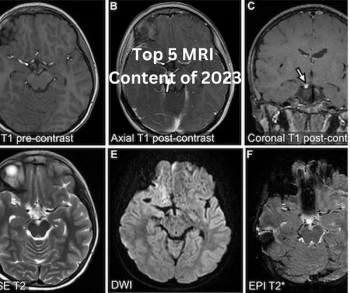

Catch up on the most well-read magnetic resonance imaging (MRI) articles from 2023.